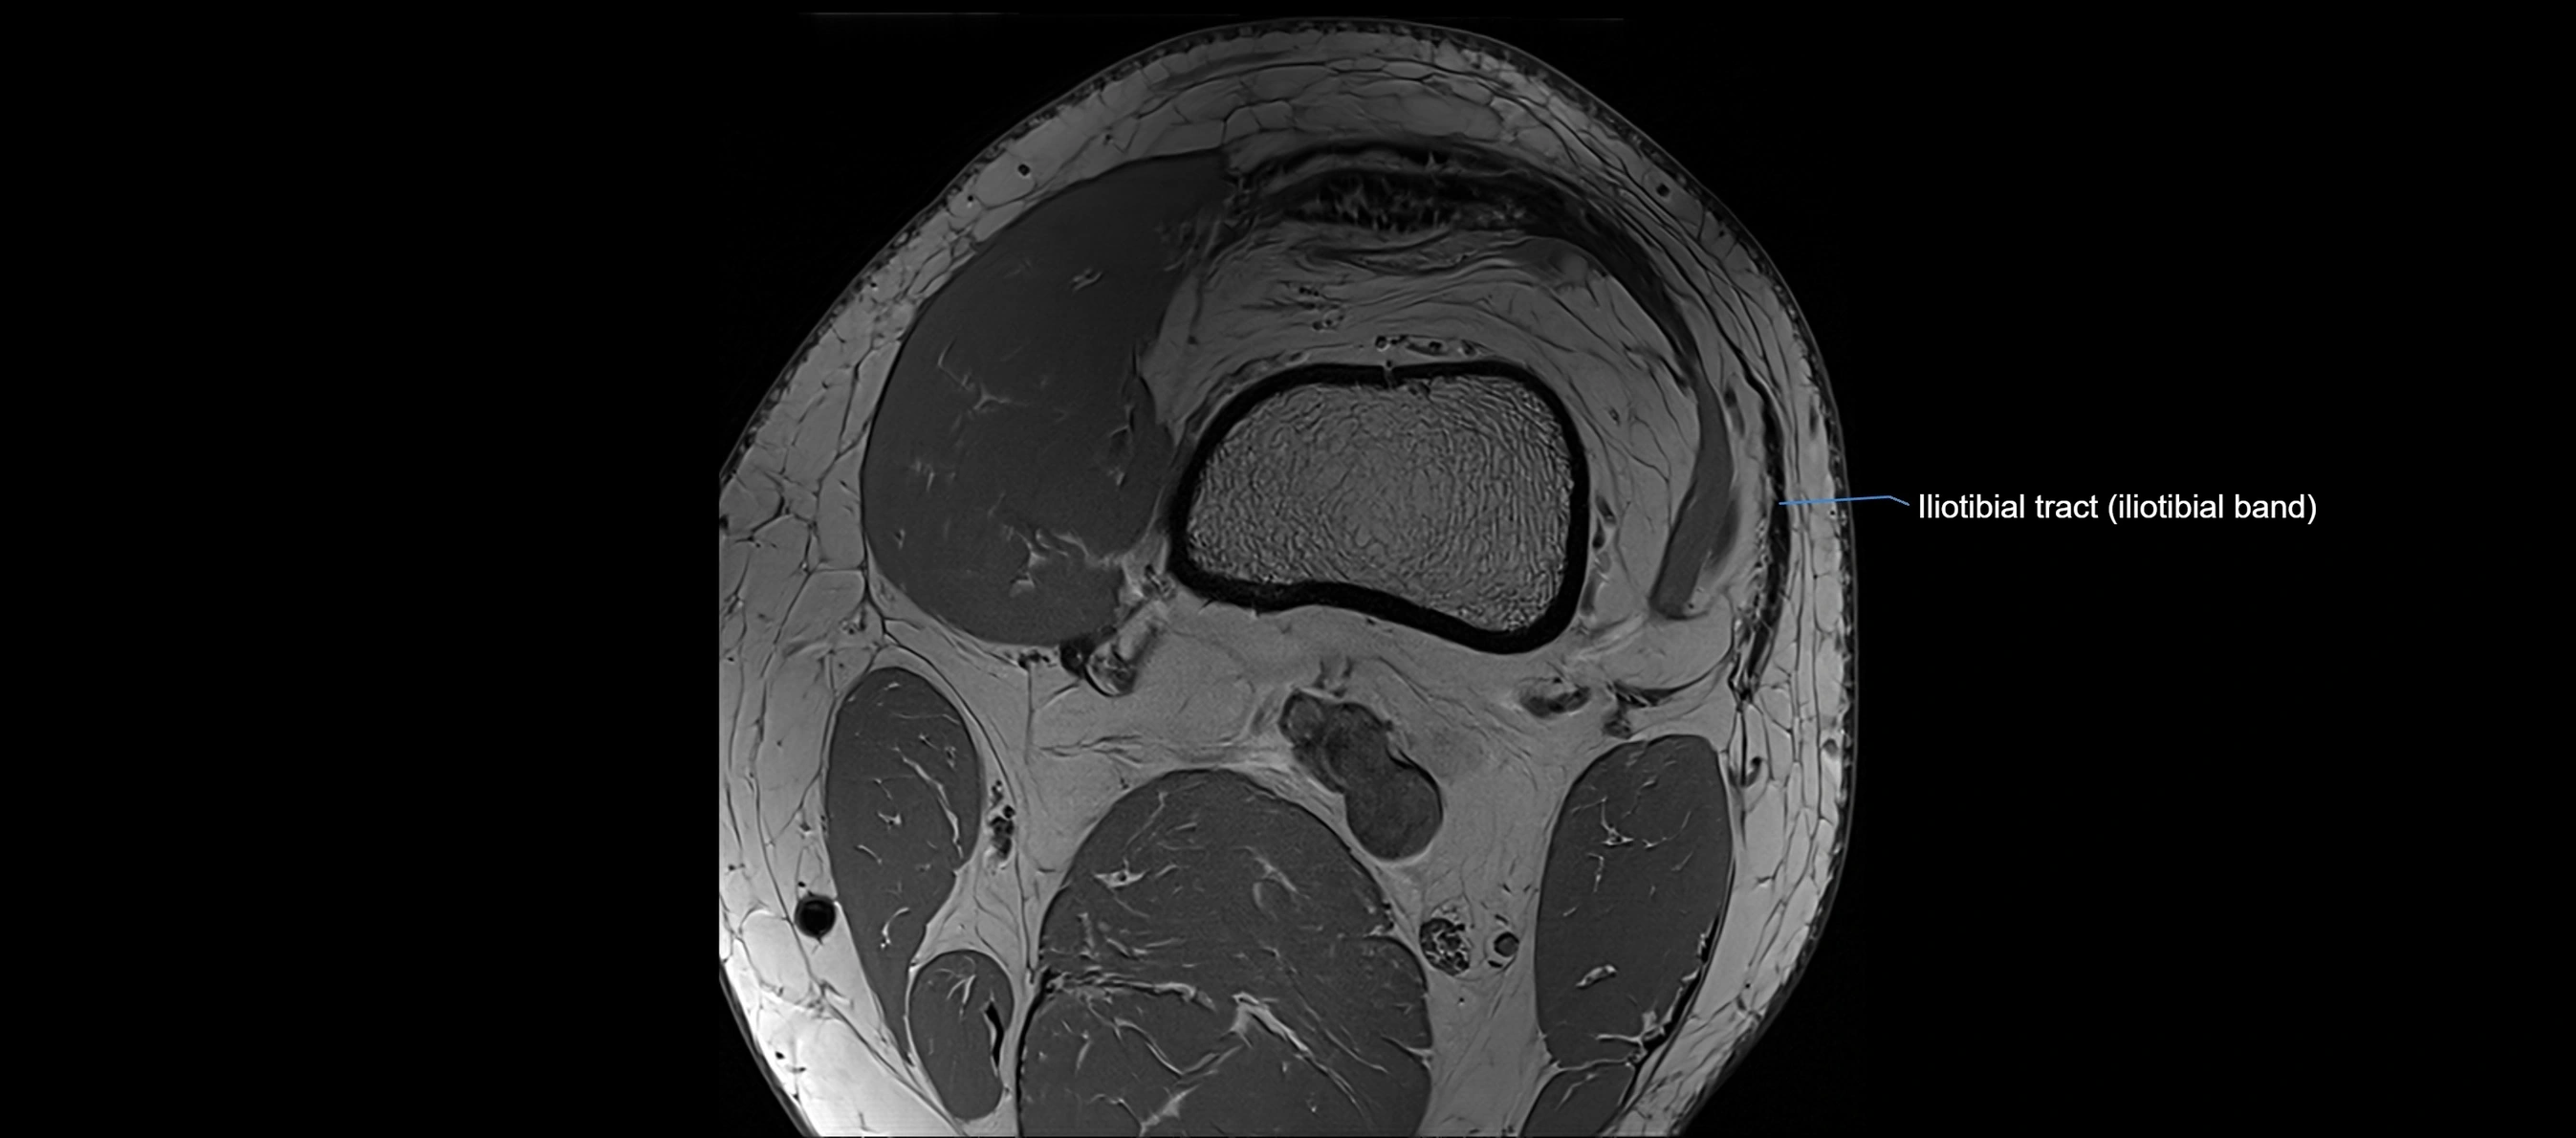

MRI images

image